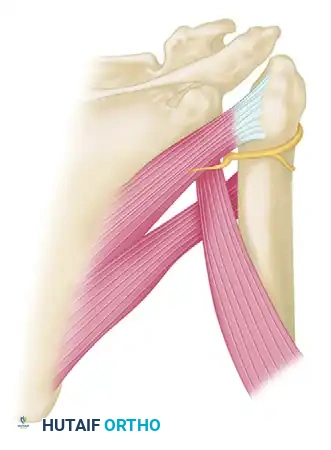

For anteromedial impression defects of the humeral head (seen in posterior dislocations), McLaughlin introduced the concept of transferring the subscapularis tendon into the defect. This effectively fills the void, preventing the defect from engaging the posterior glenoid rim during internal rotation.

- McLaughlin Technique: The subscapularis tendon is detached from its insertion, and two drill holes are placed transversely through the area of the anterior humeral defect. A mattress suture is passed through the freed tendon and the drill holes, tying it securely to fix the tendon directly into the defect.

- Neer Modification: Neer advanced this concept by performing an osteotomy of the lesser tuberosity. The subscapularis tendon, with its attached bone block from the lesser tuberosity, is mobilized and rigidly fixed into the anterior defect using a cancellous screw. This provides superior bone-to-bone healing compared to tendon-to-bone healing.

In chronic anterior dislocations, the subscapularis muscle is displaced anteriorly and inferiorly. This creates a severe traction injury to the axillary nerve. The nerve becomes entrapped and tethered—held above by the brachial plexus cords and held below where it wraps tightly behind the surgical neck of the humerus through the quadrangular space.

During the anterior approach, the surgeon must meticulously identify and protect the axillary nerve at the inferior border of the subscapularis before any capsular release or tendon transfer is performed. Aggressive retraction in this scarred bed can easily result in permanent denervation of the deltoid muscle.